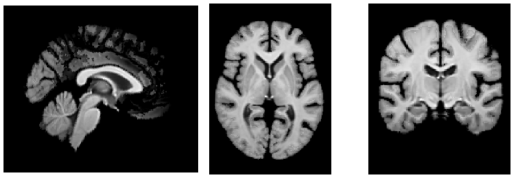

Figures 5 and 6 show visualizations for templates produced by AtlasMorph and the AtlasMorph-Uncond variants. Supplemental Figure 15, and Figure 16 show templates optimized using ANTs. The Aladdin templates are shown in Supplementary Figure 17 and Figure 18. The learned AtlasMorph templates are significantly sharper than the average of the population, shown in Figure 4.

Conditional AtlasMorph captures variability across age that a single unconditional template cannot. For example, younger subjects have more grey matter, and ventricles get larger as subjects grow older. The intensities of the atlas involve contrast changes that are consistent with segmentation boundaries, capturing the alignment between the intensity templates and the segmentation templates. We include additional visualizations of templates conditioned on age, sex and disease (cognitively normal - mild cognitive impairment - Alzheimer’s disease) in the Supplemental Material, Figure 21.